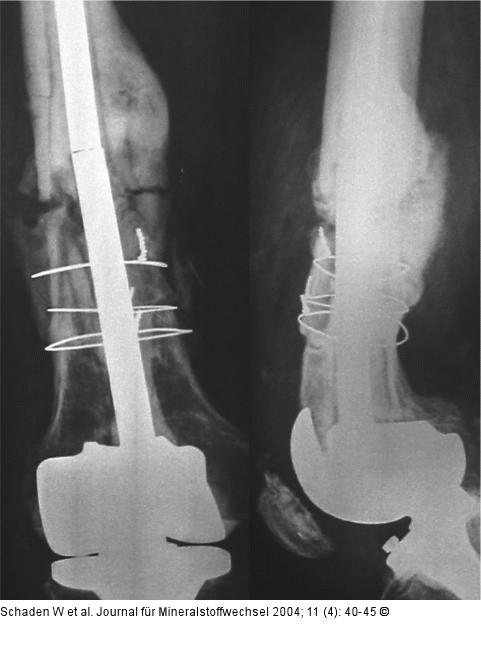

Abbildung 1: Kniegelenksprothese

Röntgenbilder eines 58jährigen Patienten, der im Juni 1996 bei Gonarthrose mit Kniegelenksprothese versorgt wurde. Im März 2000 erlitt er eine suprakondyläre Oberschenkelschaftfraktur, die primär mit Doppelplatte und zementierter Knieprothese stabilisiert wurde. Bereits im Mai 2000 kam es zum Implantatsversagen und zur Re-Verplattung. Nach neuerlichem Plattenbruch erfolgte im Juli 2000 die Implantation einer zementierten Langschaftprothese und Stabilisierung der Fraktur mittels Drahtcerclagen. Wegen Bildung einer hypertrophen Pseudarthrose wurde der Patient im Oktober 2000 im Unfallkrankenhaus Meidling vorgestellt. |